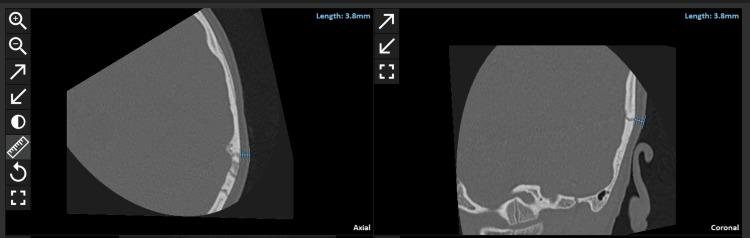

Objectives Preoperative image analysis of skin flap thickness and determining the required magnet strength are important in the management of CI surgery. The primary aim of this study is to analyze the application of OTOPLAN®, a tablet-based otological preplanning tool, in assessing skin flap thickness. The secondary aim was to determine if there is any correlation between the skin flap thickness and the selected magnet strength. Methods Fifty-seven computer tomography (CT) image datasets of temporal bones of cochlear implant (CI) patients were collected. CE marked OTOPLAN planning otology software was used to load the patient's preoperative images for measuring the skin flap thickness in both axial and coronal views. To standardize the skin flap thickness measurement, the top of the pinna on the side of implantation was taken as the measurement point. Results The mean age of the patients was 7.98 ± 1.54 years. The body mass index (BMI) was not considered in this study. The average skin flap thickness was 4.5 ± 1.2 mm (range: 2-7 mm). The inter-rater reliability test revealed strong agreement between the two reviewers (Cronbach's alpha = 0.90). The majority of the patients were fitted with a magnet strength of 3. A statistically significant positive correlation was observed between the skin flap thickness and the age of the patients (r = 0.69, p = 0.002). Also, between the skin flap thickness and the magnet strength, a strong positive correlation was observed (r = 0.82, p < 0.0001). Conclusions OTOPLAN® is a reliable tool in the measurement of skin flap thickness with little effort. The age and the magnet strength were positively correlated with the skin flap thickness.

目的 术前对皮瓣厚度进行图像分析并确定所需的磁体强度在人工耳蜗(CI)手术管理中至关重要。本研究的主要目的是分析基于平板电脑的耳科术前规划工具OTOPLAN®在评估皮瓣厚度方面的应用。次要目的是确定皮瓣厚度与所选磁体强度之间是否存在任何相关性。方法 收集了57例人工耳蜗植入患者颞骨的计算机断层扫描(CT)图像数据集。使用经CE认证的OTOPLAN规划耳科软件加载患者的术前图像,以在轴向和冠状视图中测量皮瓣厚度。为了标准化皮瓣厚度测量,将植入侧耳廓顶部作为测量点。结果 患者的平均年龄为7.98±1.54岁。本研究未考虑体重指数(BMI)。皮瓣平均厚度为4.5±1.2毫米(范围:2 - 7毫米)。评分者间可靠性测试显示两位评估者之间有很强的一致性(Cronbach's alpha = 0.90)。大多数患者配备的磁体强度为3。观察到皮瓣厚度与患者年龄之间存在统计学上显著的正相关(r = 0.69,p = 0.002)。此外,在皮瓣厚度与磁体强度之间观察到很强的正相关(r = 0.82,p < 0.0001)。结论 OTOPLAN®是一种可靠的工具,用于测量皮瓣厚度,且操作简便。年龄和磁体强度与皮瓣厚度呈正相关。